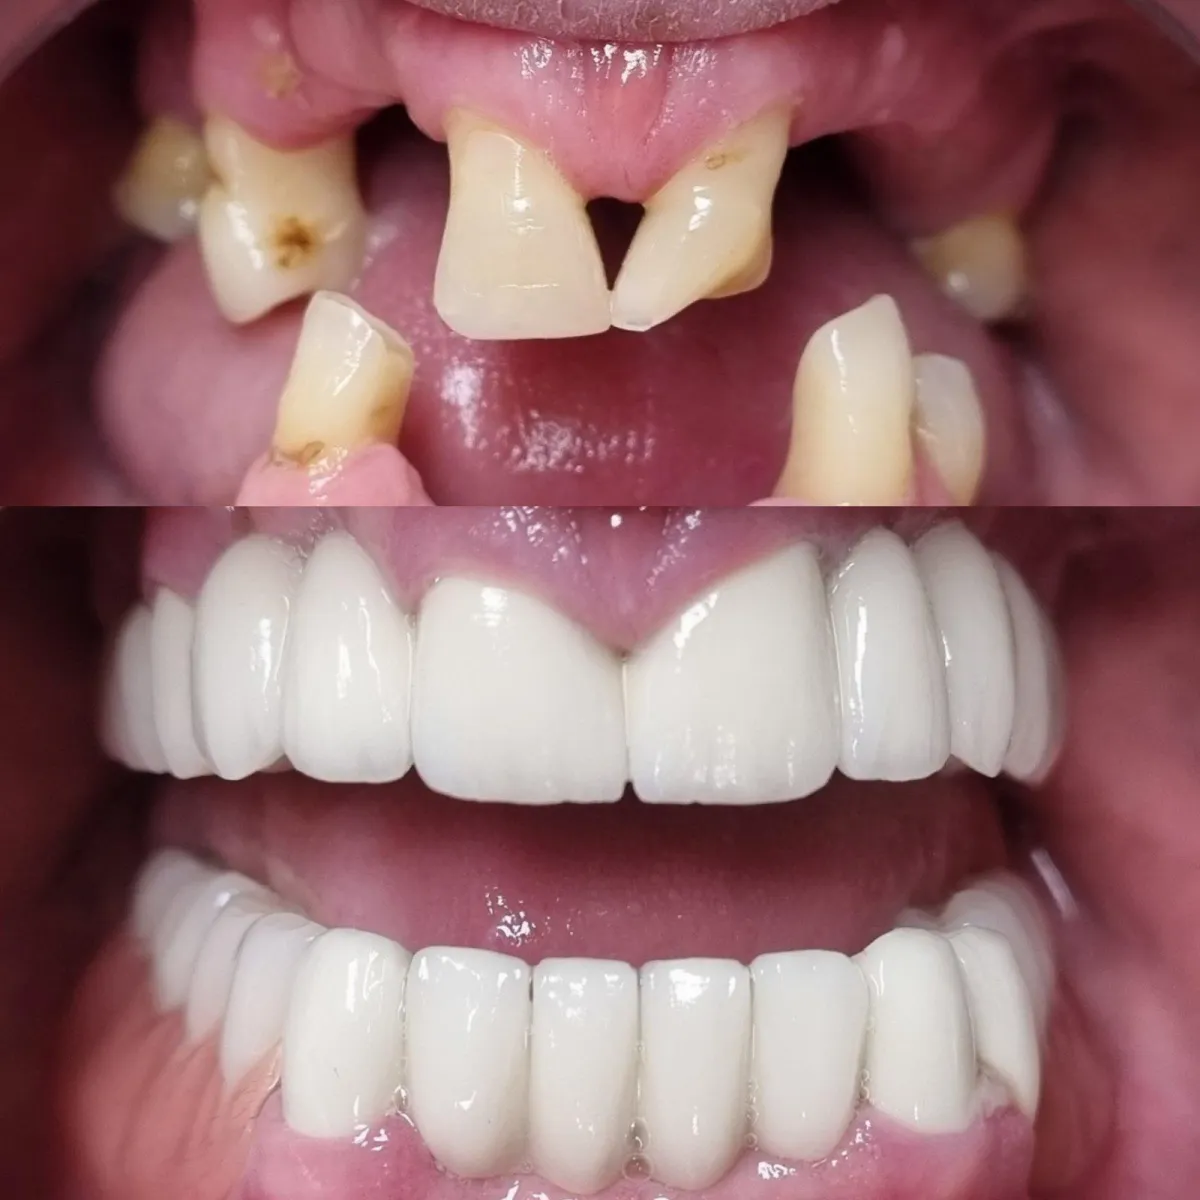

Pogledajte našu galeriju istaknutih radova u Dental Studio dr. Jusić. S ponosom vam predstavljamo rezultate našeg truda, stručnosti i posvećenosti. Bilo da se radi o estetskim zahvatima, implantatima ili ortodontskim tretmanima, naši zadovoljni pacijenti su najbolji dokaz kvalitete naših usluga.